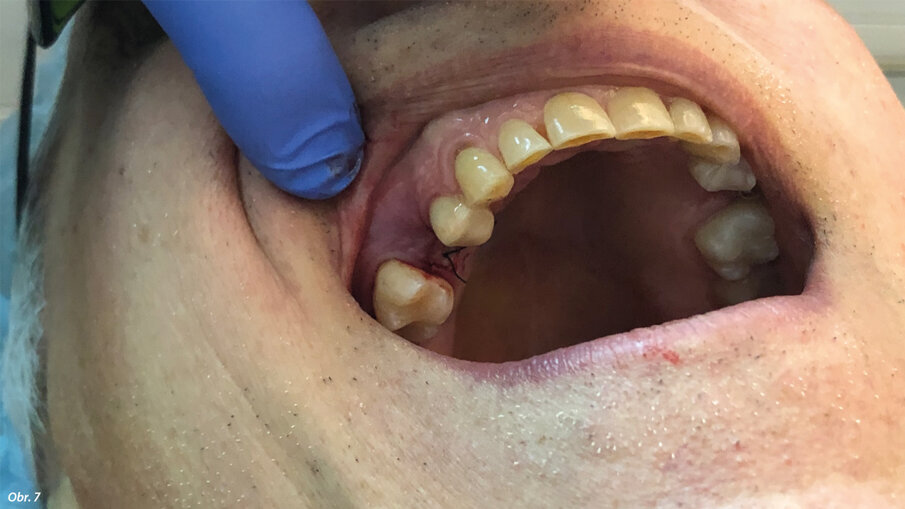

Dále byl použit Er:YAG laser s vlnovou délkou 2940 nm (LightWalker AT) opatřený digitálně kontrolovaným násadcem (X-Runner, Fotona) (obr. 4). Laser byl použit za parametrů 380 mJ a 20 Hz, působících v superkrátkých pulzech (50 mikrosekund). Byl použit externí zdroj sterilního fyziologického roztoku skladovaného při 5 °C v chladničce a tento roztok byl přiváděn pomocí peristaltické pumpy kvůli podpoře fototermické ablace a snížení teploty v místě zákroku. Digitálně kontrolovaný násadec umožňuje naprogramování a přesné provedení kruhové osteotomie o průměru 3,5 mm, tedy stejného průměru jako je poslední vrták dodávaný výrobcem implantátu. Během osteotomie byla pomocí milimetrové sondy kontrolována hloubka zavádění, až do dosažení předem nastavené hloubky 12 mm. Autor raději zavádí implantáty subkrestálně o 2 mm hlouběji, aby se předešlo resorpci v důsledku náklonu osy implantátu a bylo možno mít větší kontrolu nad emergence profilem náhrady. Byl zaveden kónický šroubový implantát vyrobený z titanu IV. třídy s opískovaným a kyselinou naleptaným povrchem (HELI, IDC). Implantát měl největší průměr 4,2 mm u vnějšího závitu a délku 10,0 mm. Po zavedení byl pomocí násadce Osstell (obr. 5, 6) určen kvocient stability implantátu (ISQ). Lalok byl sešit (obr. 7), byl pořízen RTG snímek (obr. 8) a stehy byly odstraněny po pěti dnech. V té době byl pacient požádán, aby zhodnotil pooperační bolest, kterou pociťoval, a to formou sdělení přiřazené číselné hodnoty od 0 do 10.

Obr. 8: RTG snímek pořízený bezprostředně po zákroku. Obr. 9: RTG snímek pořízený po osmi měsících zatížení.

Celkový klinický čas potřebný pro preparaci osteotomie byl zhruba 7 minut. Implantát měl v době zavedení vysokou hodnotu primární stability: hodnota ISQ naměřená v bukolingválním směru byla 84 a hodnota naměřená v meziodistálním směru byla 81. Nahlášená číselná hodnota týkající se pooperační bolesti byla 1. Ve druhé fázi implantologického ošetření, která byla provedena po 40 dnech, byly zjištěny nové hodnoty ISQ, a to bukolingválně 84 a meziodistálně 82. Po třech měsících se tyto hodnoty ještě zvýšily na 86 bukolingválně a 84 meziodistálně. Kontrolní RTG snímek pořízený po osmi měsících zatížení ukazoval na úplnou oseointegraci implantátu s velmi dobrým zhojením kosti kolem krčku abutmentu (obr. 9).